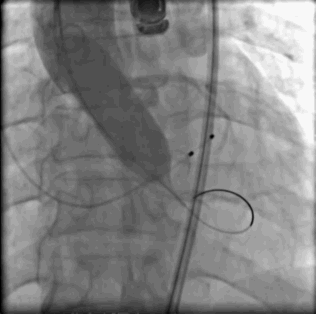

术中常规肝素抗凝。选取右侧股动脉为主路,穿刺左侧股动脉指引右侧行微穿刺,植入18F血管鞘。穿刺右侧颈内静脉植入右心室心尖临时起搏器。完成主动脉根部测压126/66mmHg,行主动脉根部造影。使用5F JR4导管带直头导丝成功跨瓣。交换猪尾导管测左室压力209/2mmHg。交换超硬导丝入左室,沿导丝送入CVB23*45mm球囊跨主动脉瓣,右室超速起搏180bmp,球囊扩展主动脉瓣并行主动脉根部造影评估球扩效果及冠脉风险。提示右冠脉显影欠佳,穿刺右侧桡动脉植入6F血管鞘,送JR4 GC至右冠脉口,沿GC送runthrough导丝至右冠脉远端,沿导丝送maverick2.0*20mm球囊至右冠脉内保护。沿加硬导丝送入VENUS A 29瓣膜及输送系统成功跨瓣,以左侧股动脉猪尾导管送至主动脉窦底部做标记,右室超速起搏120bmp,精准定位并释放瓣膜,期间反复猪尾造影确定瓣膜位置,撤出输送系统。复测主动脉根部压力125/55mmHg,左室心尖:125/10mmHg,主动脉根部造影左右冠显影清晰。在造影下缓慢退出股动脉长鞘,缝合并加压包扎双侧股动脉,术闭。

主动脉根部猪尾造影左右冠显影正常

球囊预扩造影右冠显影不明显右冠保护